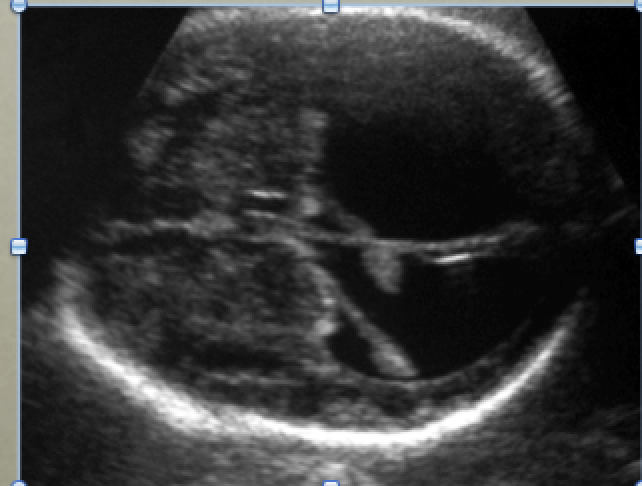

Otherwise well baby with macrocephaly

Imaging abnormality and likely etiology?

Hydrocephalus and congenital aqueductal stenosis

Large lateral ventricles with “dangling choriod plexus sign”